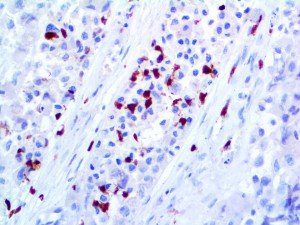

It is the ICU physician who is most likely to witness one of the deadliest manifestations of the abnormal immunological response, the cytokine storm syndrome (CSS). This response is also referred to by some as the cytokine release syndrome (CRS). CSS is characterized by continuous activation and expansion of macrophage and lymphocyte populations, which secrete large amounts of cytokines, causing the cytokine storm. This massive cytokine release is akin to hemophagocytic lymphohistiocytosis (HLH) disease, a syndrome characterized by initial unchecked and persistent activation of cytotoxic T lymphocytes and NK cells.

Clinical and laboratory manifestations of HLH include fever, enlarged liver and/or spleen, neurologic dysfunction, coagulopathy, liver dysfunction, cytopenias (i.e., low levels of erythrocytes, leukocytes, and/or platelets), hypertriglyceridemia, hyperferritinemia, hemophagocytosis, and eventually diminished NK cell activity as the immune system becomes progressively paralyzed. HLH can be familial (primary HLH) or secondary to another disease process (sHLH), such as rheumatic disease, in which it is referred to as macrophage activation syndrome (MAS, characterized by elevated ferritin).